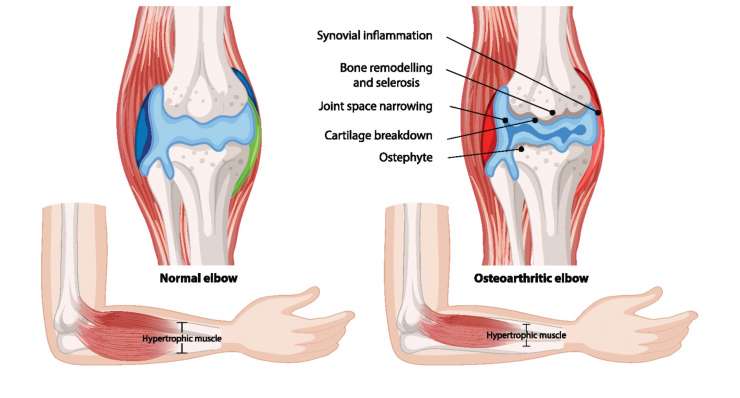

артроз локтя

Артроз локтевого сустава, то есть износ суставного хряща, сначала лечится профессором, доктором медицины Франком Мартешлегером консервативными методами, а при запущенной стадии — артроскопически или с помощью современных протезов локтевого сустава.